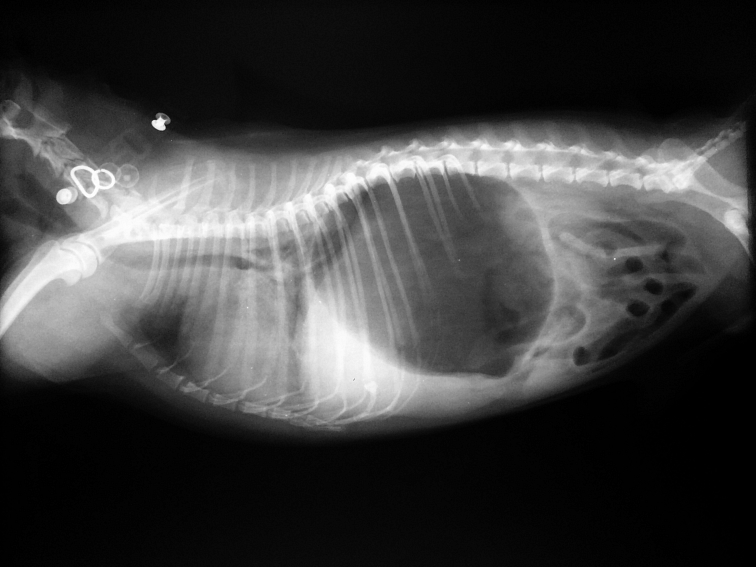

Pri torzi žalúdka sú dôležité minúty. Je to akútny stav, ktorý sa rieši ihneď a čo najskôr! Stav sa musí stabilizovať, a to nie je možné vyriešiť inak než doviesť psa k veterinárovi, ktorý vykoná operáciu. Zavedením vhodnej kanyly na podanie tekutín, medikácie a liekov proti bolesti.

Odstránenie plynov buď zavedením žalúdočnej sondy alebo punkciou brucha ihlou (gastrocentéza). Následne prichádza operačný zákrok, kedy sa žalúdok musí otočiť do pôvodnej polohy (detorzia) a prišiť k brušnej stene, aby sa zabránilo opakovaniu torzie. Následná rekonvalescencia trvá približne 3 mesiace.